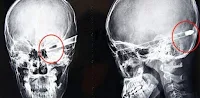

O mototaxista baleado na cabeça, durante assalto Parnaíba,Antônio Edílson de Araújo Xavier, de aproximadamente 50 anos, conhecido Antônio “Sabiá”, começou a se queixar de que não estava mais enxergando nada, que estava cego.

A médica lavou o rosto da vítima soro fisiológico e foi possível ver duas perfurações do lado direito.

Uma próxima do olho e outra próxima do ouvido.